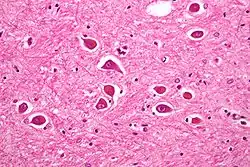

Hepatisk encefalopati eller Coma hepaticum (undertiden forkortet HE) er den medicinske betegnelse for levercoma. Det er en akut tilstand, med påvirket hjernefunktion og forskellige somatiske symptomer, forårsaget af leversygdom. Tilstanden varierer i omfang, fra let konfusion til bevidstløshed (koma) og kan være både akut og kronisk betinget.